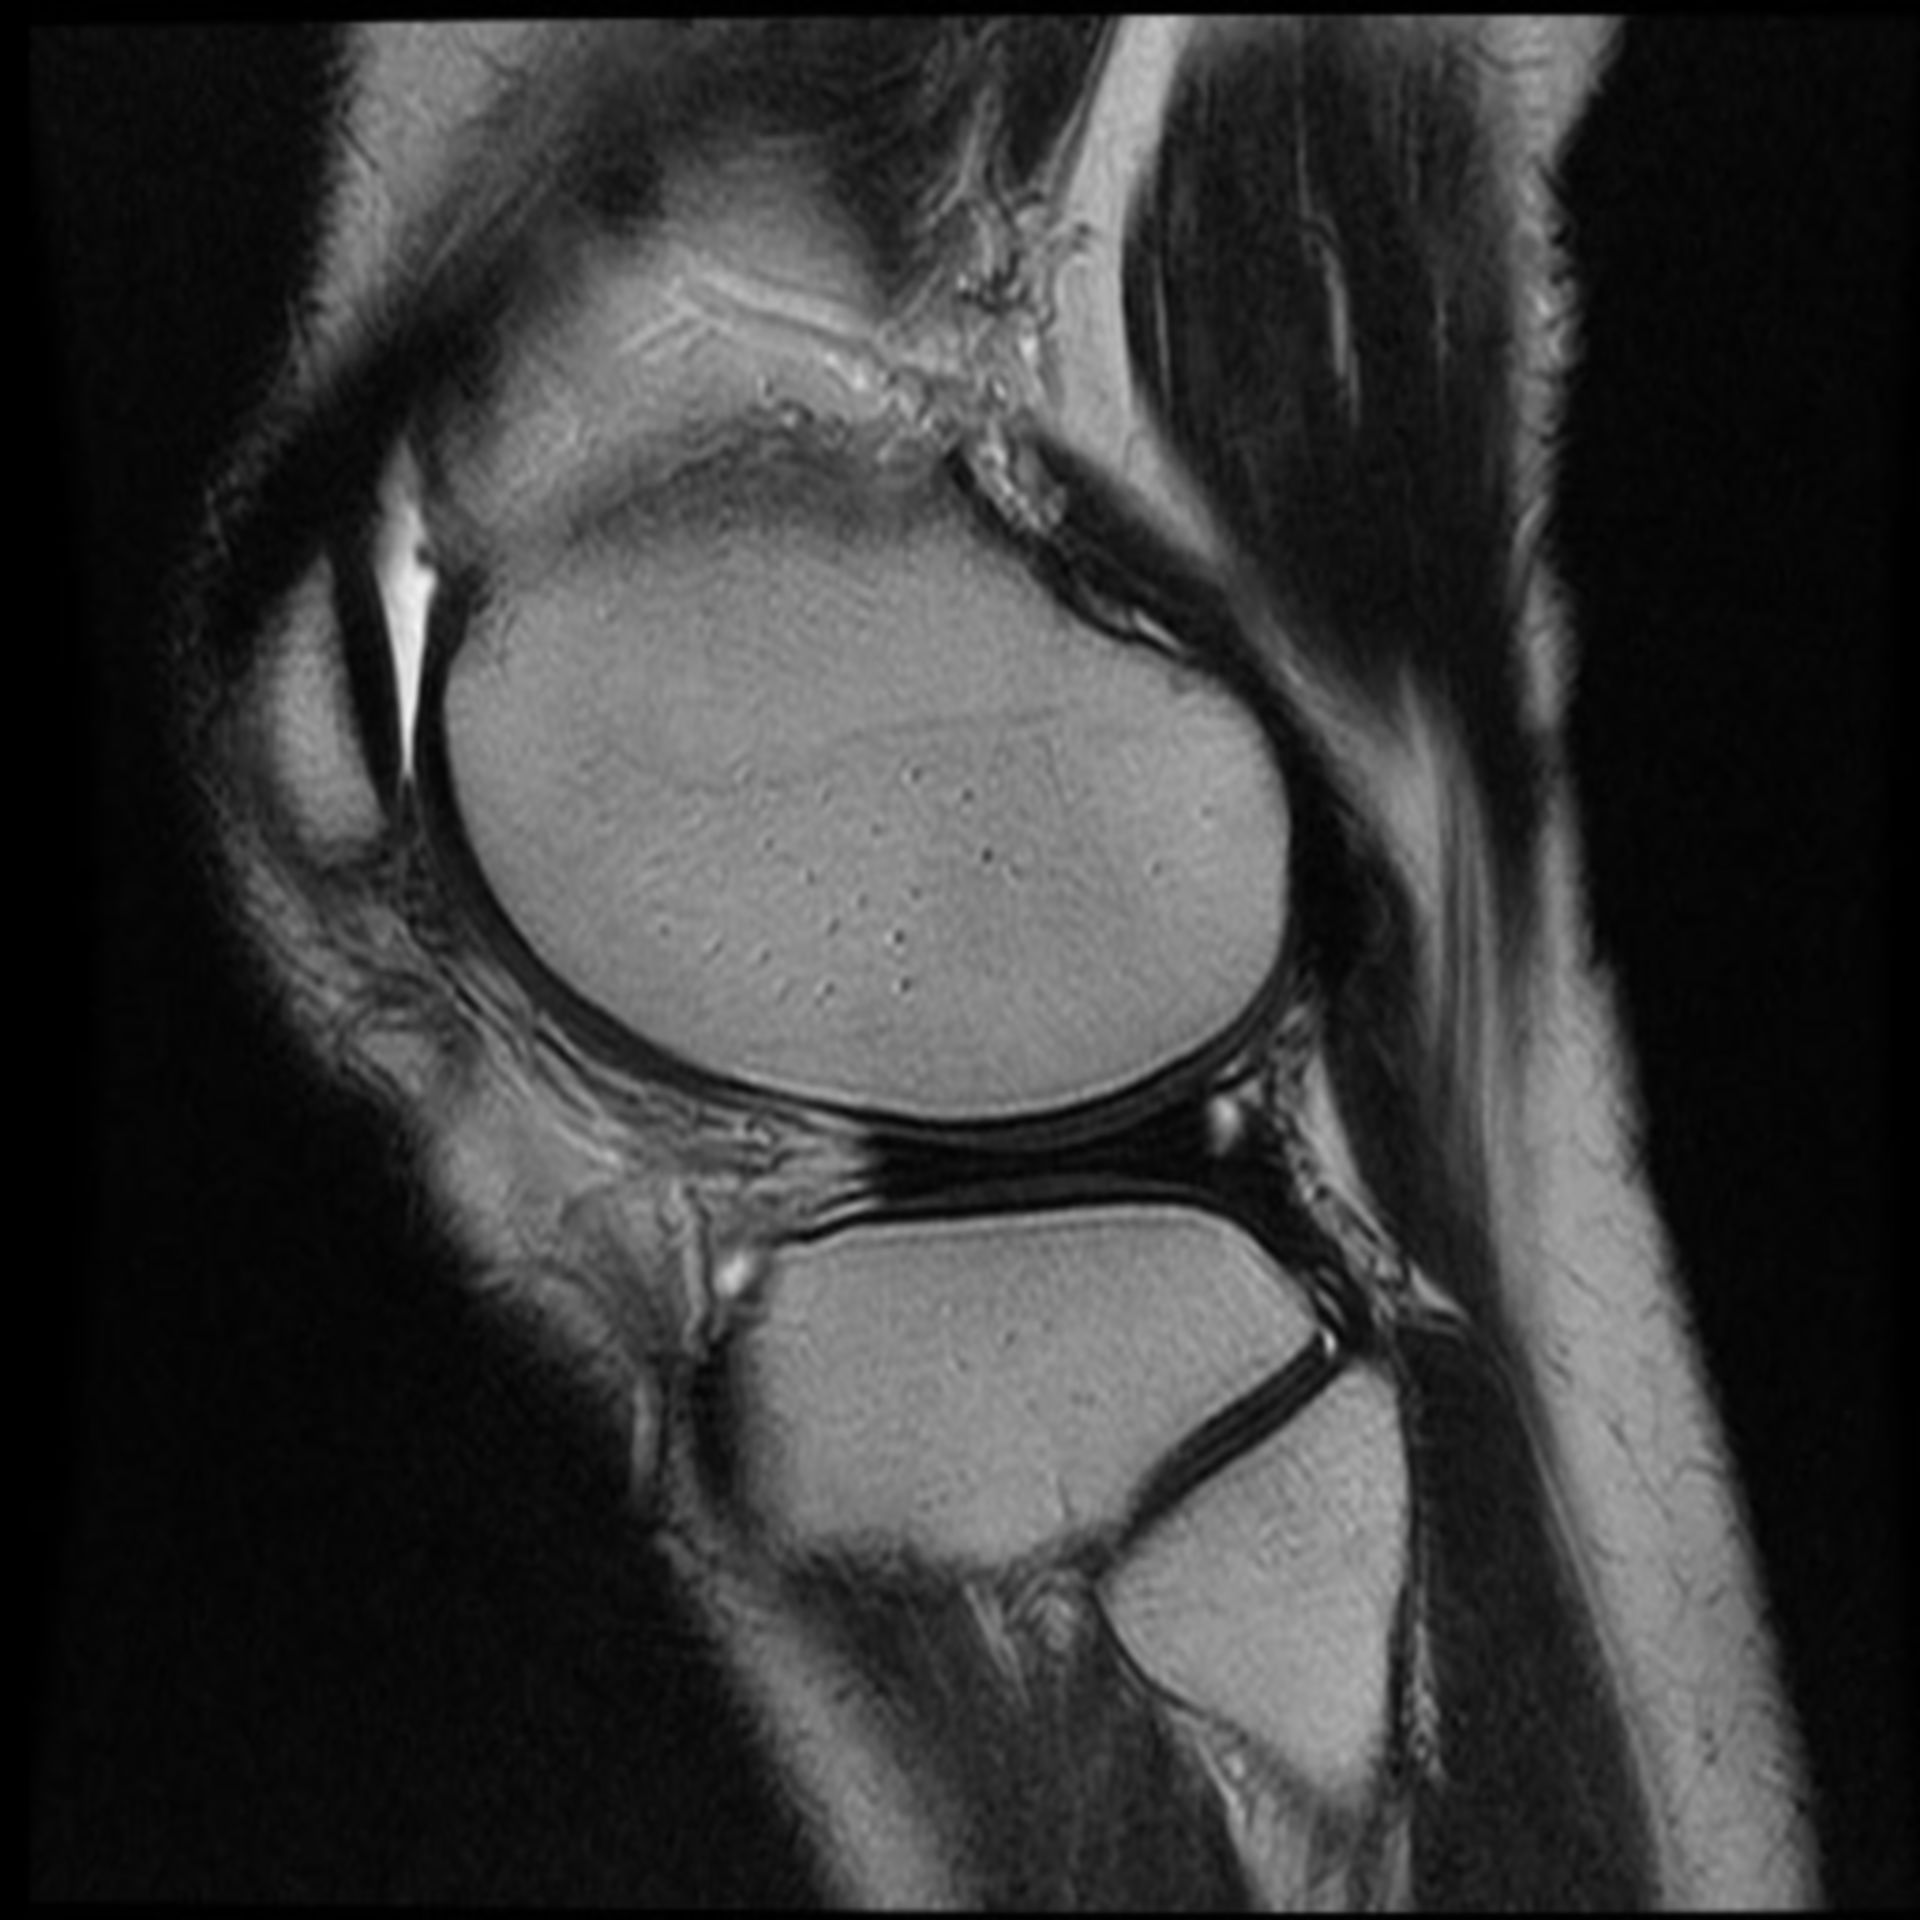

MRT Knie – DocCheck MRT Niere3 – DocCheck

MRT: Knie – DocCheck MRT in der Krebsmedizin

MRT Knie links HWS ARTHROSE, MRT Stockfotografie – Alamy

Kreuzbandriss im MRT – Privatpraxis Dr. med. Severin Welter รีวิว 1441 Meal Box (MRT อิสรภาพ) – เนื้ออร่อยมา บรรจุปลอดภัย สะอาด – Wongnai

MRT Knie links MRT der akuten MS Stockfotografie – Alamy

Mrt Bilder – Meniskusriss? (Knie, Orthopädie, Chirurgie) (16/34) MRT Schädel in Sagittalebene, T₂‐gewichtet – DocCheck

MRT Knie links Mrt Bilder Schulter Sehnenriss – Captions Blog

MRT: Knie – DocCheck MRT Schädel – DocCheck

Knee Joint Mri Stockfotos und -bilder Kaufen – Alamy MRT Thorax – DocCheck

MRT: Knie – DocCheck MRT Knie links

MRT Knie linksสถานีMRTแทบแตก? คนเยอะมาก รถไฟไทย🇹🇭พามาดูความลึกความยาวสถานีสามยอดไทยสร้างได้ไง!ความลึกเท่าตึก3ชั้น😯